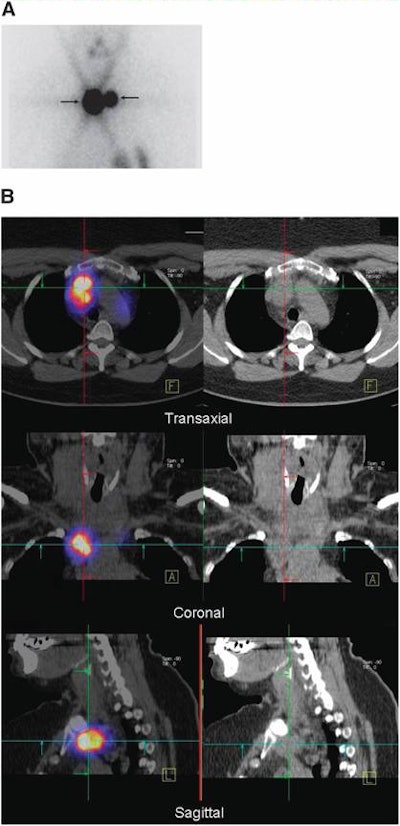

![]() |

| Fifty-four-year-old woman with differentiated papillary thyroid carcinoma after total thyroidectomy and lymph node dissection of centrocervical and left lateral compartment. Image A is planar scintigraphy, which shows two iodine-131-avid foci interpreted as thyroid remnant. Image B is SPECT/CT (left column) and CT (right column), which demonstrate that these foci correspond to lymph node metastases in the superior mediastinum. Images courtesy of the Journal of Nuclear Medicine and University of Erlangen-Nürnberg. |